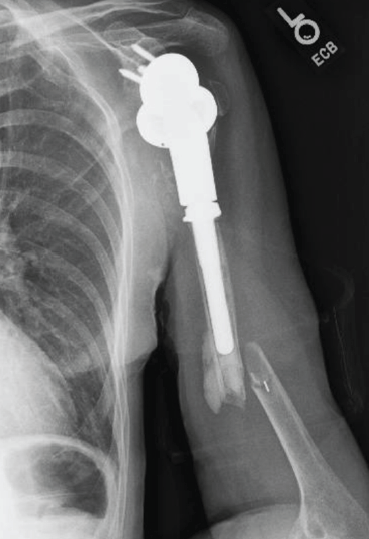

Figure 2: Anteroposterior radiograph taken after reverse total shoulder arthroplasty.

RTSA was performed under general anesthesia with an interscalene block for pain relief using the Comprehensive Reverse Shoulder System (Zimmer Biomet, Warsaw, Indiana, USA). The lesser and greater tuberosity fragments were mobilized, and no. 5 sutures (Ti-Cron, Medtronic, Minneapolis, Minnesota, USA) were placed at the bone-tendon interface to prevent comminution of the fragments. The glenoid baseplate and glenosphere were placed without difficulty despite soft glenoid bone. A distal cement restrictor was placed, and the implant was cemented into the humerus. Multiple variations of the glenoid tray and polyethylene components were used to create stability within the system construct. The tuberosities were secured to the humeral shaft using no. 5 sutures (Ti-Cron), which were placed before cementing (Fig. 2). No intraoperative complications were noted.